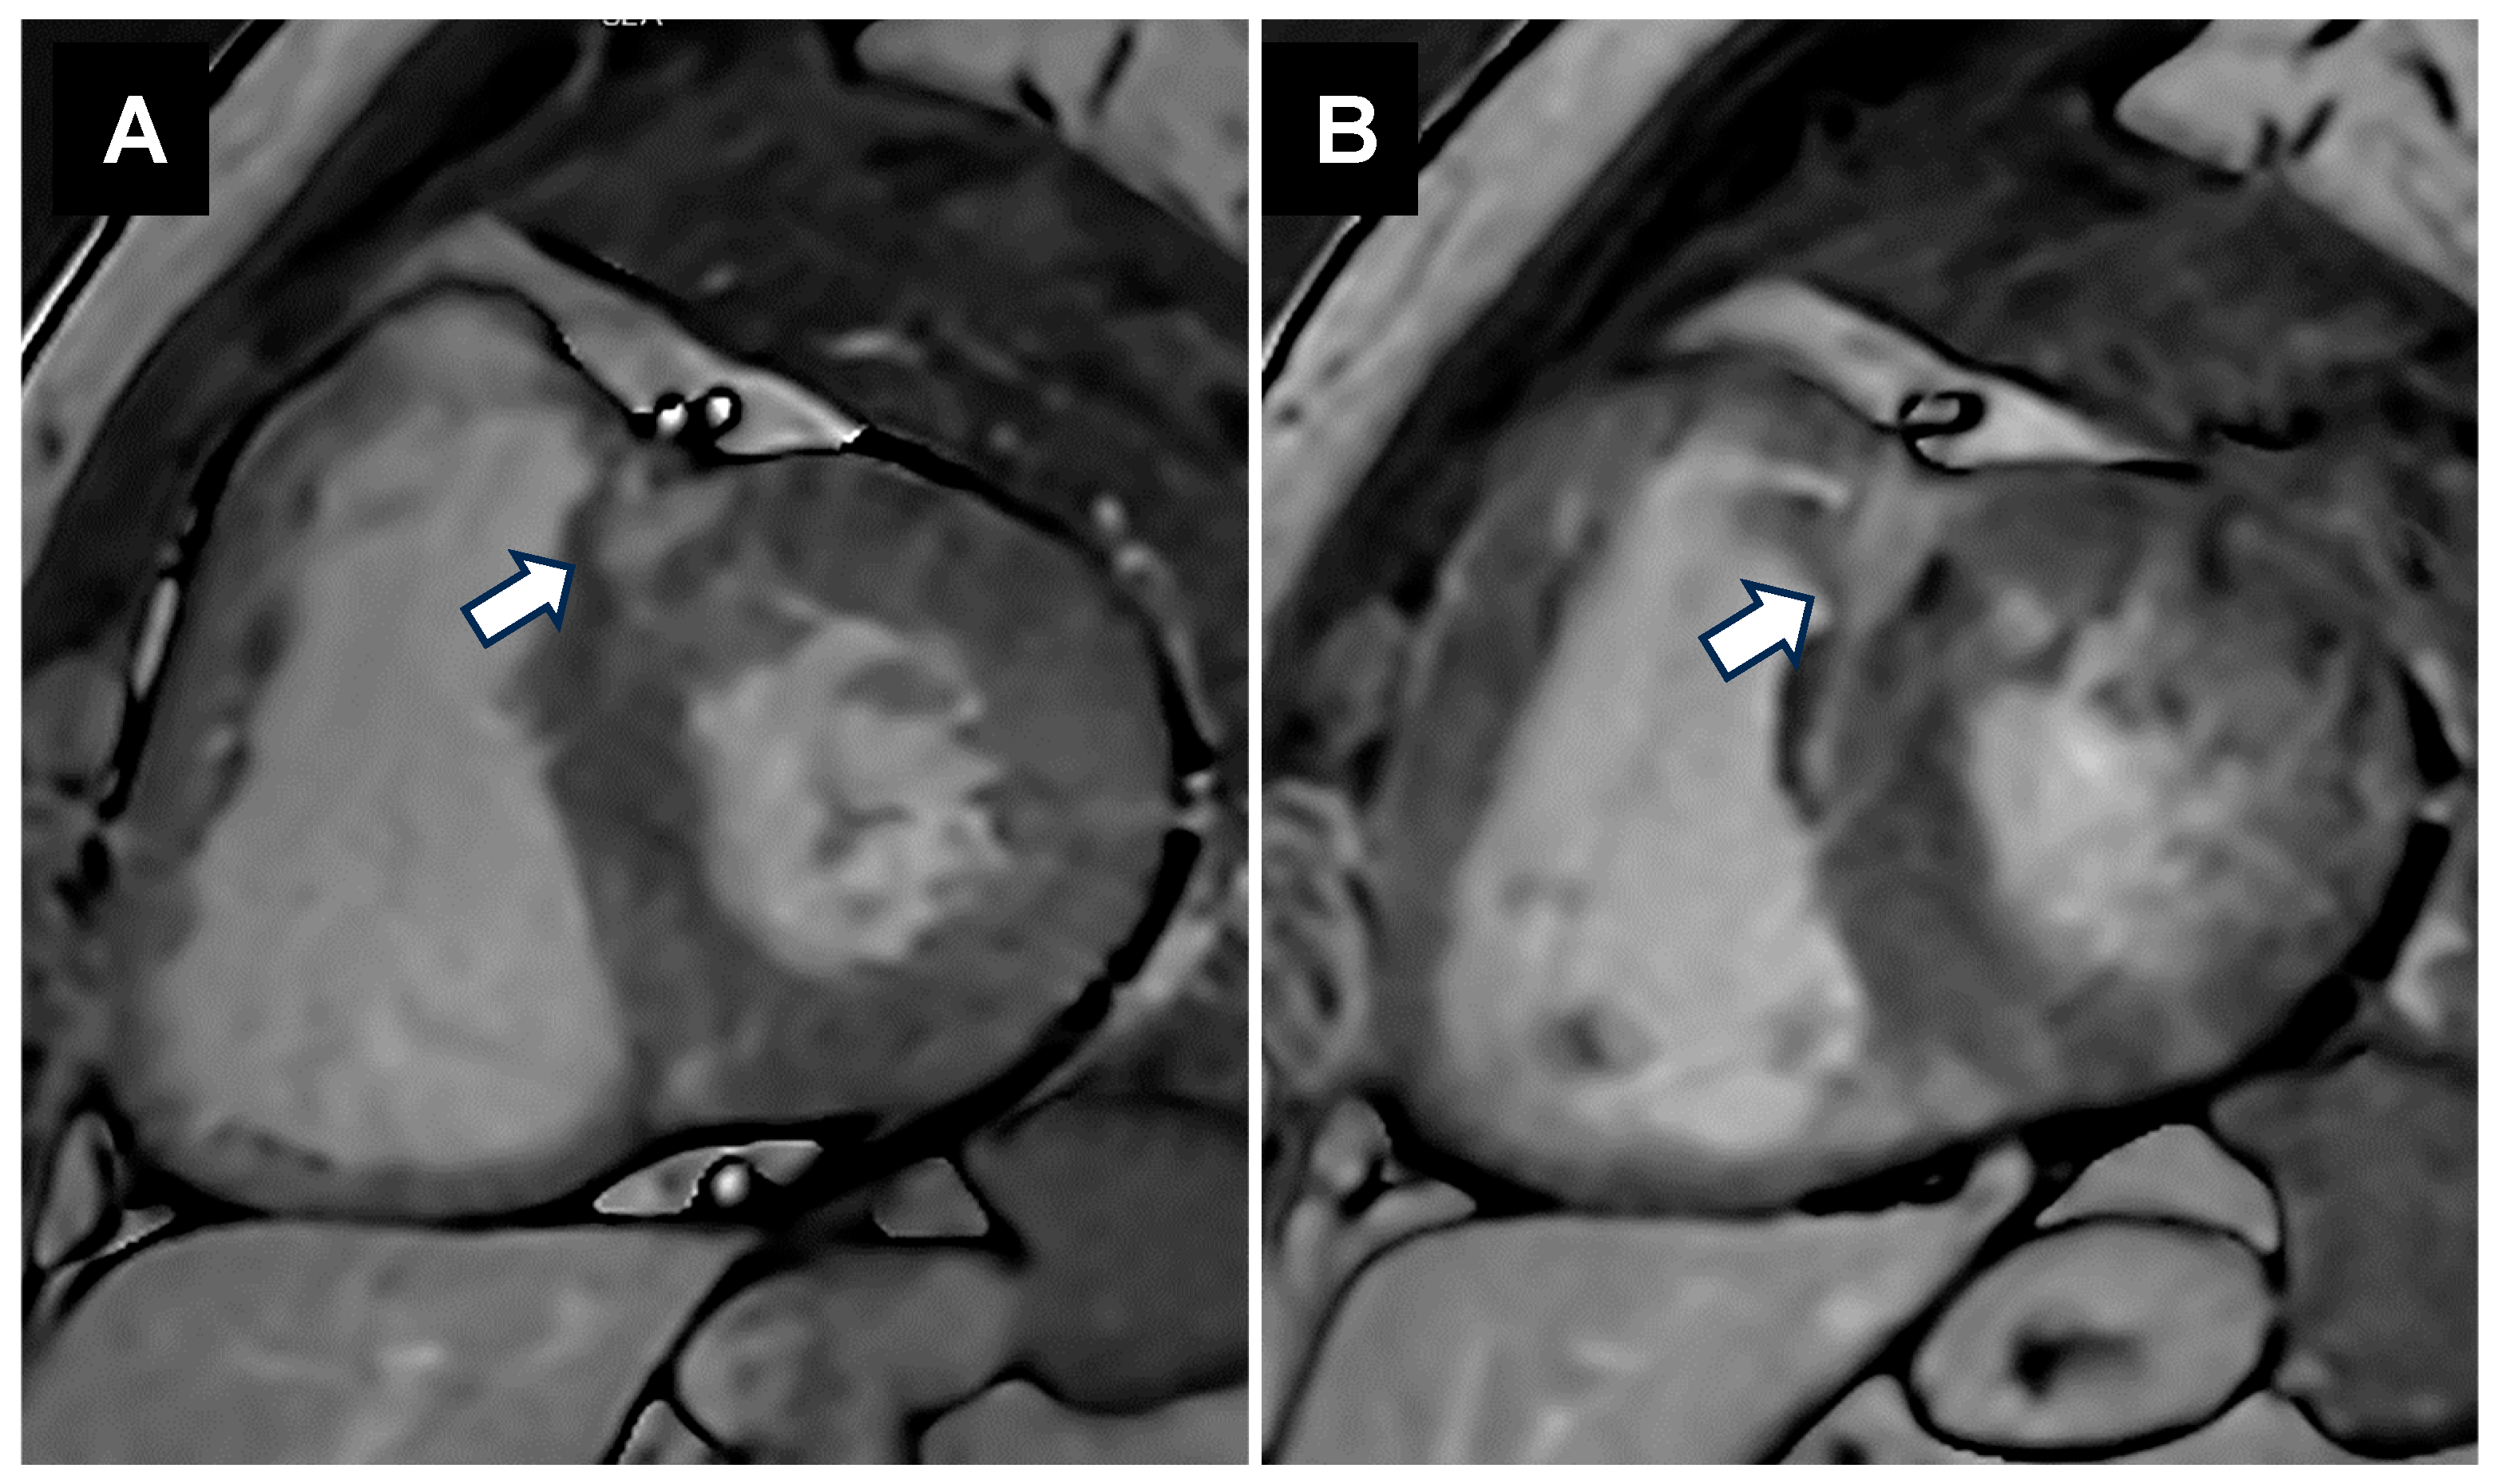

- Putra, T.M.H.; Sukmawan, R.; Elen, E.; Atmadikoesoemah, C.A.; Desandri, D.R.; Kasim, M. Prognostic Value of Late Gadolinium Enhancement in Postoperative Morbidity following Mitral Valve Surgery in Rheumatic Mitral Stenosis. Int. J. Angiol. 2019, 28, 237–244. [Google Scholar] [CrossRef]

- Elen, E.; Atmadikoesoemah, C.A.; Kasim, M.; Klinis, P. Effect of Myocardial Fibrosis on Left Ventricular Function in Rheumatic Mitral Stenosis: A Preliminary Study with Cardiac Magnetic Resonance. Indones. J. Cardiol. 2017, 38, 202–206. [Google Scholar] [CrossRef]

- Soesanto, A.M.; Desandri, D.R.; Haykal, T.M.; Kasim, M. Association between late gadolinium enhancement and global longitudinal strain in patients with rheumatic mitral stenosis. Int. J. Cardiovasc. Imaging 2019, 35, 781–789. [Google Scholar] [CrossRef] [PubMed]

- Galli, E.; Lancellotti, P.; Sengupta, P.P.; Donal, E. LV mechanics in mitral and aortic valve diseases: Value of functional assessment beyond ejection fraction. JACC Cardiovasc. Imaging 2014, 7, 1151–1166. [Google Scholar] [CrossRef]

- Lee, Y.S.; Ching-Ping, L. Ultrastructural Pathological Study of Left Ventricular Myocardium in Patients with Isolated Rheumatic Mitral Stenosis with Normal or Abnormal Left Ventricular Function. Jpn. Heart J. 1990, 31, 435–448. [Google Scholar] [CrossRef]